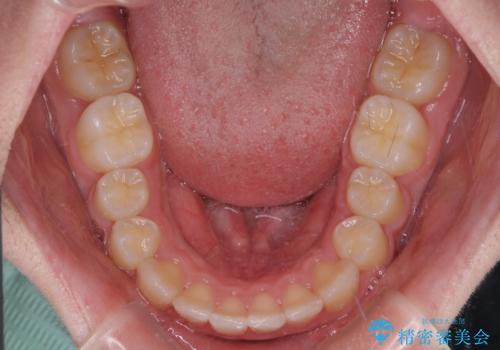

中学生のワイヤー矯正 クロスバイトを短期間で改善

叢生のため磨き残しの多い歯列でしたが、1年弱で治療を終了でき、磨き残しや歯肉の腫れが著しく改善されました。